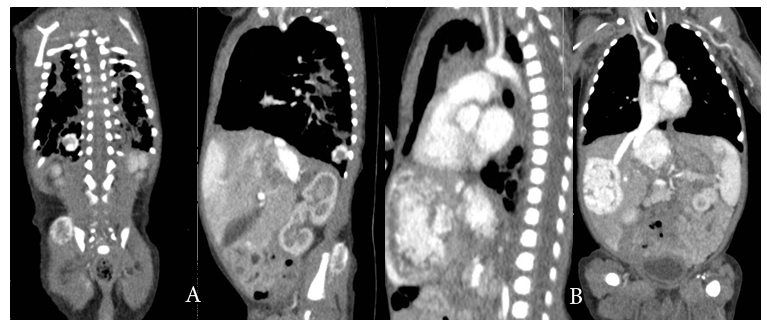

On day 30 of life baby started to show red papular lesions over palm of right hand, left shoulder and pubic region, each sized about two mm (Figure 1 A, B and C) for which the following investigations were done:Ultrasonography of the abdomen revealed multiple oval hypo‒echoic lesions of different sizes. The largest lesion measured around 3mm×3mm. Doppler examination showed the presence of feeding blood vessels (Figure 2 A and B). A CT examination of the abdomen with contrast was advised for further evaluation of the liver, to aid a differential diagnosis between hemangiomatosis, metastases, and liver abscesses. This revealed enhanced lesions with multiple foci in both the hepatic lobes with arteriovenous shunting in the form of dilated branches of the hepatic artery and prominently draining hepatic veins. It was reported that the lesions could possibly be hemangio‒endothelioma or infantile angiosarcoma. Additionally, the right basal segment of the lower lobes of the lungs and right gluteus maximus muscle revealed lesions with multiple foci, which was presumed to be a secondary deposit (Figure 3 A and  B). The tumour marker AFP (20,777 IU/mL), liver functions were normal apart from mild elevation of alkaline phosphatase (513 IU/mL), and total bilirubin (1.9 g/dL). Repeat test after a week revealed decreasing values. Fundoscopy screen on day 33 of age showed ROP stage 1 bilaterally and a repeat follow up after 2 weeks was normal and was instructed for follow up after 6 months.

Figure 3 (A) well‒defined 1.2 x 1 cm sized intensely enhancing lesion in the right lower lobe basal segments and 1.7 cm sized focal enhancing lesion noted in the right gluteal region in the gluteus maximus muscle. (B) Multiple focal variable sized intensely enhancing lesion in both hepatic lobes, the largest lesion in the medial segment of left lobe measures 3.5 x 2.7 cm. The lesion in the right hepatic lobe measures 3.3 x 2.2 cm.